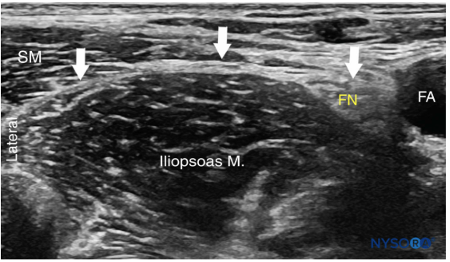

Identify the femoral artery, then slide laterally until you obtain the following view. The hyperechoic line overlying the iliopsoas is your target, the fascia iliaca.

|